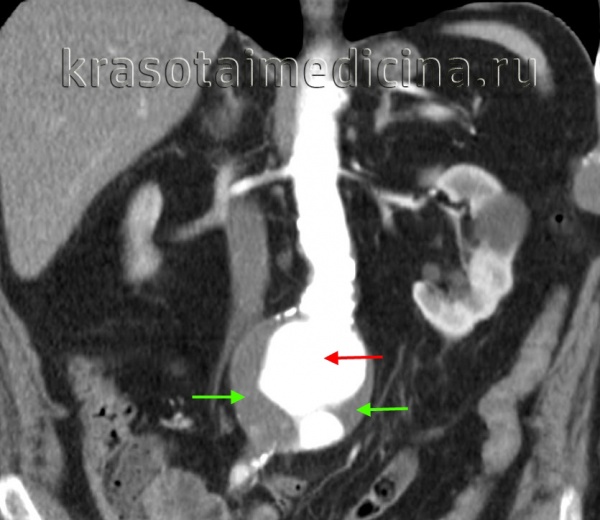

Брюшная аневризма аорты хорошо видна на рентгеновских снимках. Это связано с тем, что на аневризме накапливается кальций, который создает тень во время исследования.

Если во время УЗИ у пациента была выявлена аневризма, ему назначают магнитно-резонансную томографию (МРТ) или компьютерную томографию (КТ). Эти методы позволяют получить наиболее полную информацию о существующем дефекте.

Диагностика аневризмы аорты включает в себя анализ как субъективных, так и объективных данных, а также проведение различных рентгенологических, ультразвуковых и томографических исследований. Одним из аускультативных признаков аневризмы является наличие систолического шума в области расширенной аорты. Аневризмы брюшной аорты могут быть выявлены при пальпации живота, где они проявляются в виде пульсирующего опухолевидного образования. Инструментальная диагностика включает в себя следующие методы:

-

Рентгенография. В рамках рентгенологического обследования пациентов с аневризмой грудной или брюшной аорты проводятся рентгеноскопия и рентгенография грудной клетки, обзорная рентгенография брюшной полости, а также рентгенография пищевода и желудка. На завершающем этапе исследования выполняется аортография, которая позволяет уточнить локализацию, размеры и протяженность аневризмы, а также ее взаимосвязь с соседними анатомическими структурами.

УЗИ. Для диагностики аневризм восходящего отдела аорты применяется эхокардиография; в других случаях используется ультразвуковая допплерография (УЗДГ) грудной и брюшной аорты.

Компьютерная томография. Компьютерная томография (МСКТ) грудной и брюшной аорты предоставляет возможность точно и наглядно визуализировать аневризматическое расширение, а также выявить наличие расслоений, тромботических масс, парааортальных гематом и очагов кальциноза.

На основании результатов комплексного инструментального обследования принимается решение о необходимости оперативного вмешательства. Важно дифференцировать аневризму грудной аорты от опухолей легких и средостения, а аневризму брюшной аорты – от объемных образований в брюшной полости, поражений лимфоузлов брыжейки и забрюшинных опухолей.